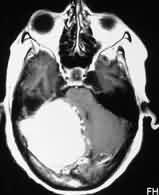

|

Bifalcine

meningioma-MRI

|

Falx meningioma-MRI

|

|

|

|

|

Convexity meningioma

with hyperostosis- MRI

|

Convexity meningioma

with hyperostosis- X-ray

|

|

|

|

|

Orbital meningioma-CT

|

Parasagittal

meningioma-MRI

|

|

|

|

|

Meningioma with

Associated pituitary adenoma-MRI

|

Olfactory groove

meningioma-MRI

|

|

|

|

|

Petrous

meningioma-MRI

|

Suprasellar

meningioma-MRI

|

|

|

|

|

Tuberculum sella

meningioma-CT

|

Diaphragm sella

meningioma-MRI

|

|

|

|

|

Meningioma with skull

infiltration-MRI

|

Intradiploic

meningioma-MRI

|

|

|

|

|

Sp. Wing en plaque

meningioma-MRI

|

Meningioma extending

through foramen ovale -MRI

|

|

|

|

|

Intraventricular

meningioma-MRI

|

Cystic meningioma

with dural tail-MRI

|

|

|

|

|

Tentorial

meningioma-MRI

|

Torcular

meningioma-MRI

|

|

|

|

|

Hemangiopericytoma-MRI

|

Jugular foramen

meningioma-MRI

|

|

|

|

|

F.M

meningioma-pre op-MRI

|

Multiple

Meningiomas -MRI

|